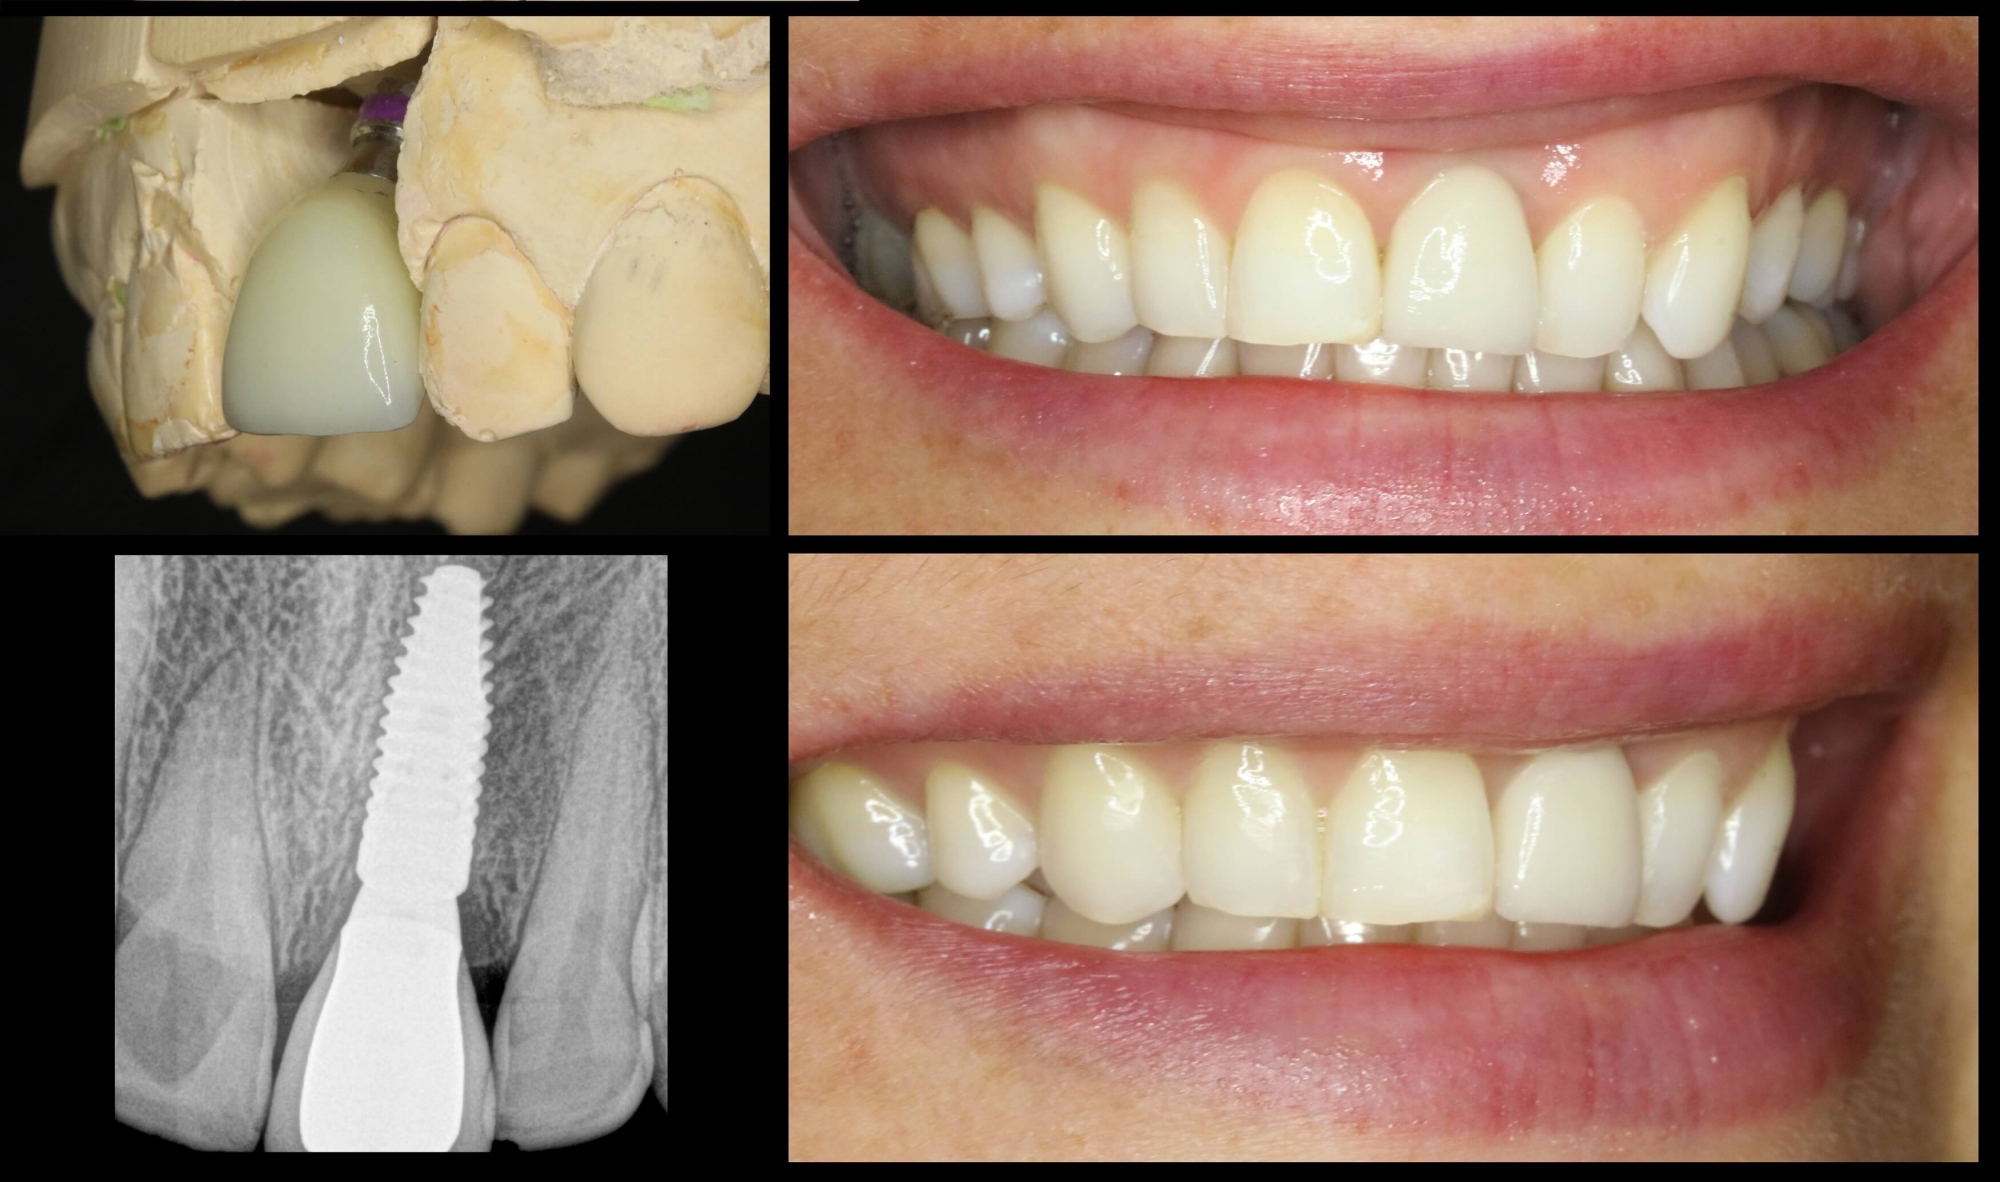

• Tūlītēja zoba implanta ievietošana un pagaidu kronīša (plastmasa) izgatavošana.

• Pēc 5 mēnešiem tika izgatavots slāņots cirkonijkeramikas kronis

• Tika  nomainītas vecās plombas priekšzobu rajonā